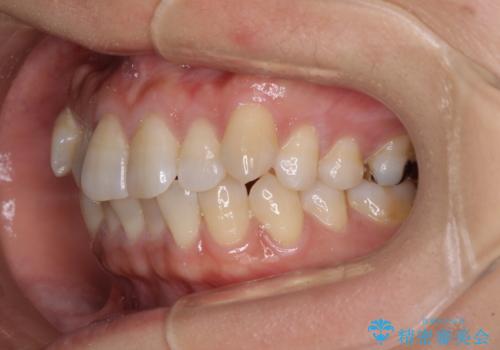

気になる八重歯 ワイヤー装置での非抜歯矯正

- 上顎の八重歯と全体的なデコボコを気にして来院された患者様です。

口元の突出感はなかったため非抜歯矯正での対応となりますが、八重歯を改善する際に上顎前歯が前突する可能性があったため、上顎臼歯部にアンカースクリューを使用して、歯列が前方に転位しないようにすることとしました。

また舌のトレーニングを行うことで、上顎前歯の突出予防や上下前歯に隙間ができなくなるようにしました。